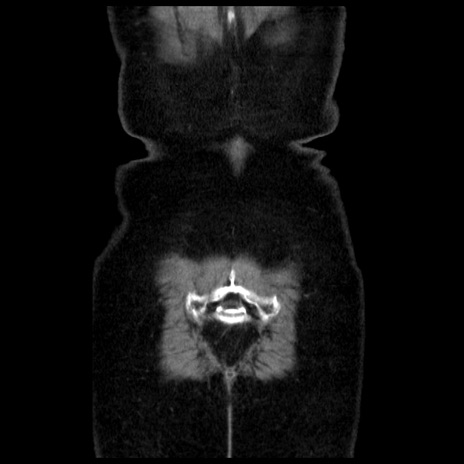

横断像